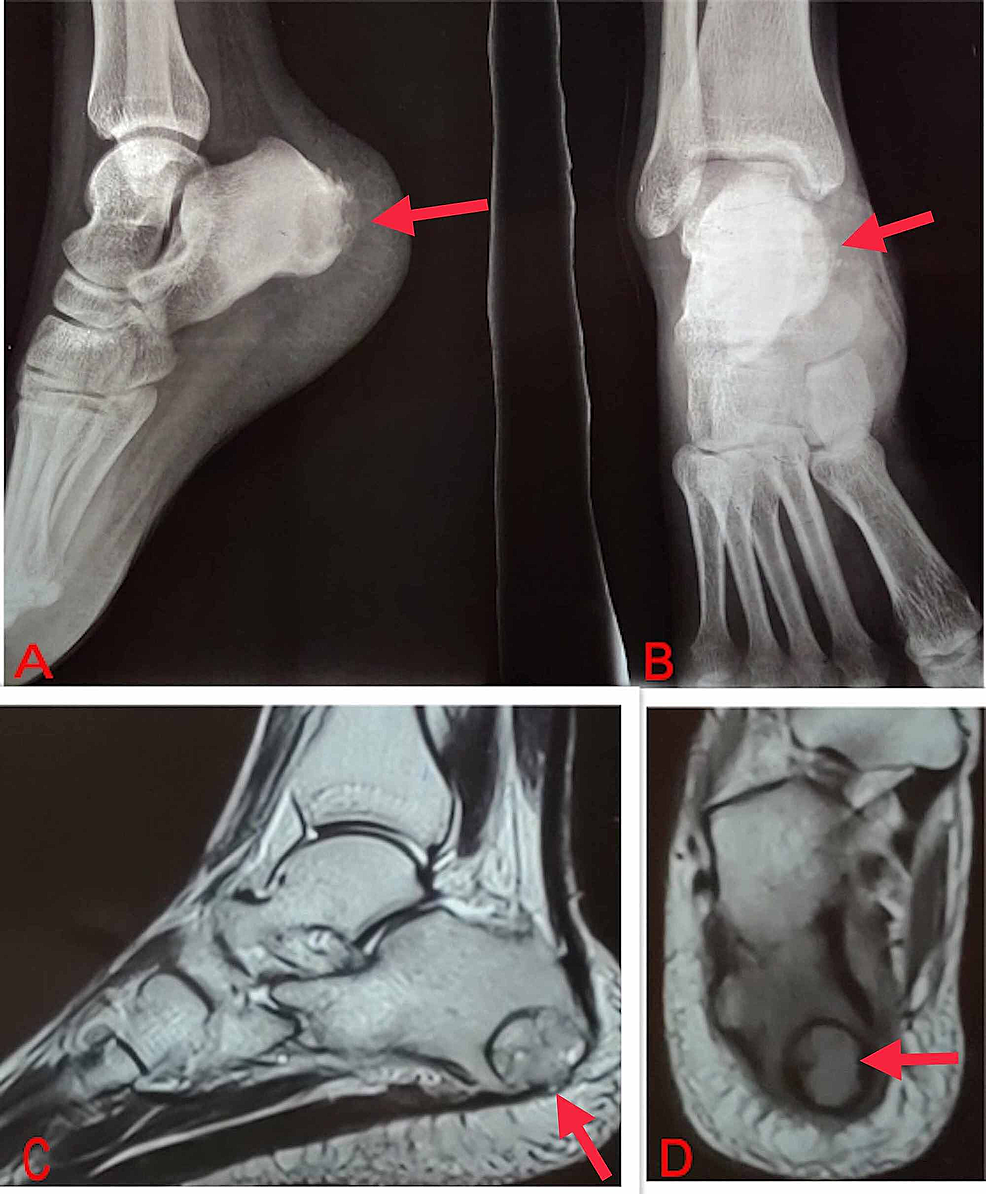

Giantcell tumour of the synovium in a facet joint in the thoracic Facet Joint Giant Cell Tumor osteolytic bone destruction in the area of the facet joint with a soft tissue mass and hypointensity on t2wi images. facet joint neoplasms like osteoid osteoma, plasmacytoma, tenosynovial giant cell tumor, and osteochondroma are best. We describe fdg pet/ct findings in a. Differentiate between giant cell tumor and other bone lesions through a comprehensive analysis. facet joint. Facet Joint Giant Cell Tumor.

Giantcell tumour of the synovium in a facet joint in the thoracic Facet Joint Giant Cell Tumor facet joint neoplasms like osteoid osteoma, plasmacytoma, tenosynovial giant cell tumor, and. Differentiate between giant cell tumor and other bone lesions through a comprehensive analysis. facet joint neoplasms like osteoid osteoma, plasmacytoma, tenosynovial giant cell tumor, and. osteolytic bone destruction in the area of the facet joint with a soft tissue mass and hypointensity on t2wi images.. Facet Joint Giant Cell Tumor.

Giantcell tumour of the synovium in a facet joint in the thoracic Facet Joint Giant Cell Tumor facet joint neoplasms like osteoid osteoma, plasmacytoma, tenosynovial giant cell tumor, and osteochondroma are best. osteolytic bone destruction in the area of the facet joint with a soft tissue mass and hypointensity on t2wi images. facet joint neoplasms like osteoid osteoma, plasmacytoma, tenosynovial giant cell tumor, and osteochondroma are best. We describe fdg pet/ct findings in a.. Facet Joint Giant Cell Tumor.

Giantcell tumour of the synovium in a facet joint in the thoracic Facet Joint Giant Cell Tumor tenosynovial giant cell tumor rarely affects the facet joints of the spine. facet joint neoplasms like osteoid osteoma, plasmacytoma, tenosynovial giant cell tumor, and osteochondroma are best. osteolytic bone destruction in the area of the facet joint with a soft tissue mass and hypointensity on t2wi images. facet joint neoplasms like osteoid osteoma, plasmacytoma, tenosynovial giant. Facet Joint Giant Cell Tumor.

Giantcell tumour of the synovium in a facet joint in the thoracic Facet Joint Giant Cell Tumor We describe fdg pet/ct findings in a. facet joint neoplasms like osteoid osteoma, plasmacytoma, tenosynovial giant cell tumor, and. Differentiate between giant cell tumor and other bone lesions through a comprehensive analysis. tenosynovial giant cell tumor rarely affects the facet joints of the spine. osteolytic bone destruction in the area of the facet joint with a soft. Facet Joint Giant Cell Tumor.

Giantcell tumour of the synovium in a facet joint in the thoracic Facet Joint Giant Cell Tumor facet joint neoplasms like osteoid osteoma, plasmacytoma, tenosynovial giant cell tumor, and osteochondroma are best. facet joint neoplasms like osteoid osteoma, plasmacytoma, tenosynovial giant cell tumor, and. osteolytic bone destruction in the area of the facet joint with a soft tissue mass and hypointensity on t2wi images. facet joint neoplasms like osteoid osteoma, plasmacytoma, tenosynovial giant. Facet Joint Giant Cell Tumor.